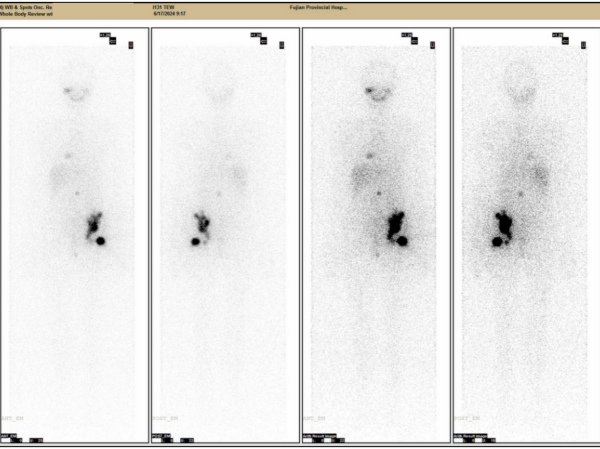

▲rhTSH辅助治疗后骨转移灶大量摄碘131,预示将取得好的治疗效果